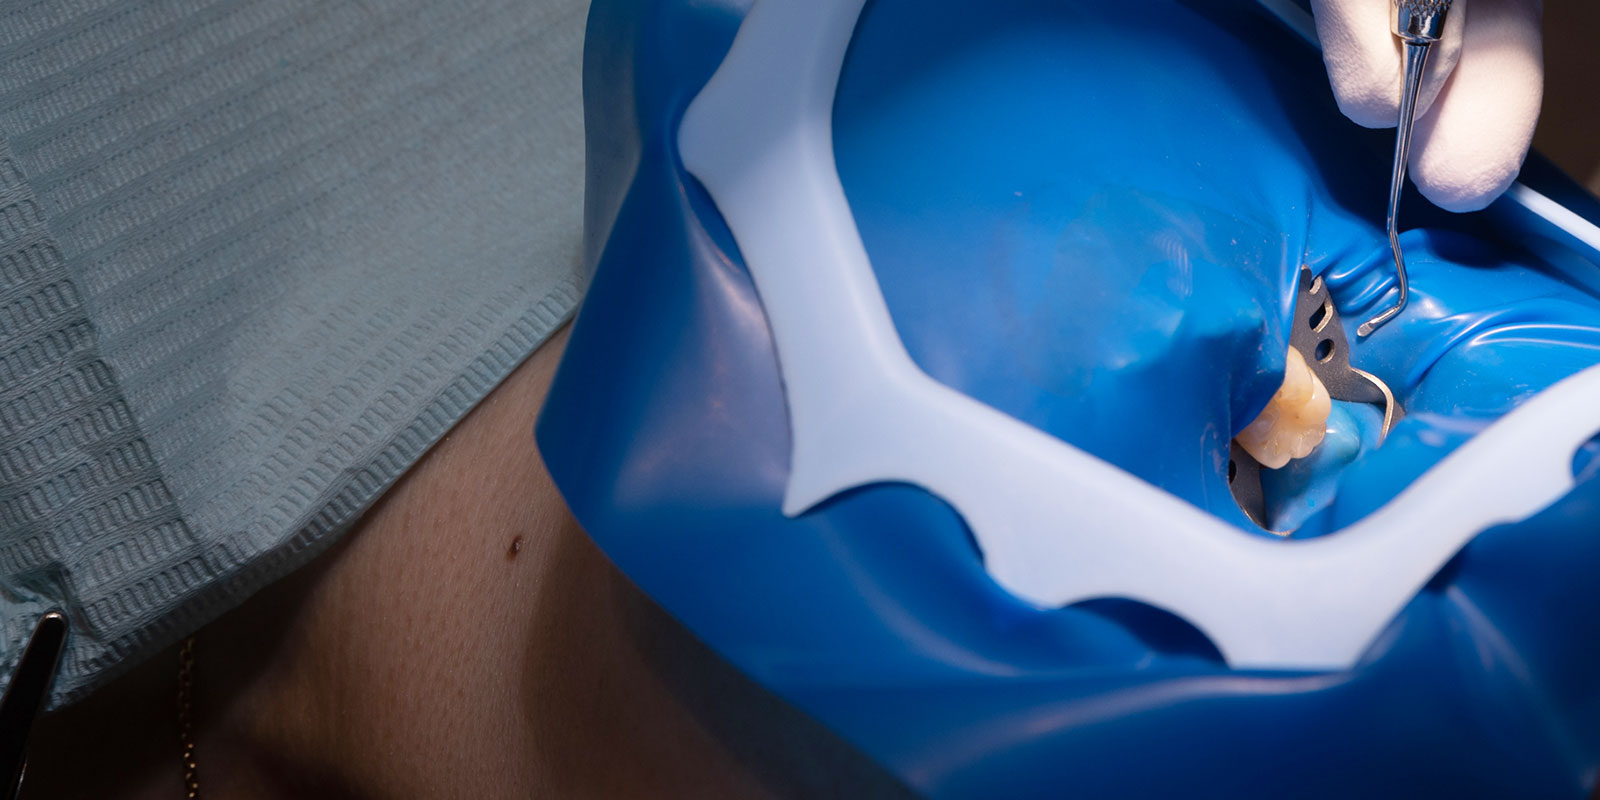

治療時の大切な歯を

細菌から守ります

「ラバーダム」というものをご存知でしょうか?

治療している歯に唾液が流れ込まないようにするゴムのシートがラバーダムです。

歯の治療は、常に唾液で濡れてしまう環境で行うため、唾液と一緒に細菌が侵入してきたり、水気によって詰め物の接着が悪くなったりしてしまいます。良い治療を提供するためにはラバーダムが必須になるため、しちご歯科ではご希望の方には積極的にラバーダムの使用をおすすめしております。